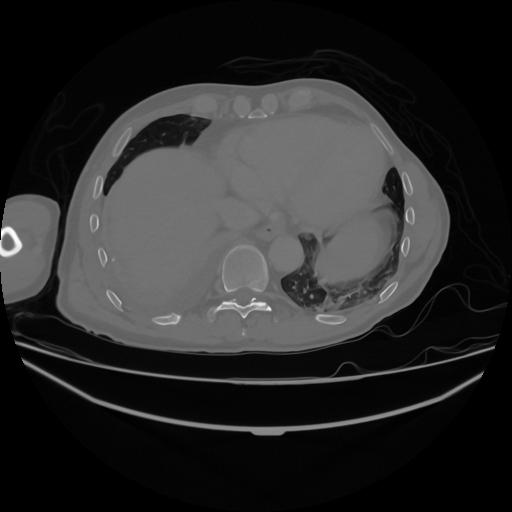

5 CUERPO,CE,Vol,1.0,CUERPO,,